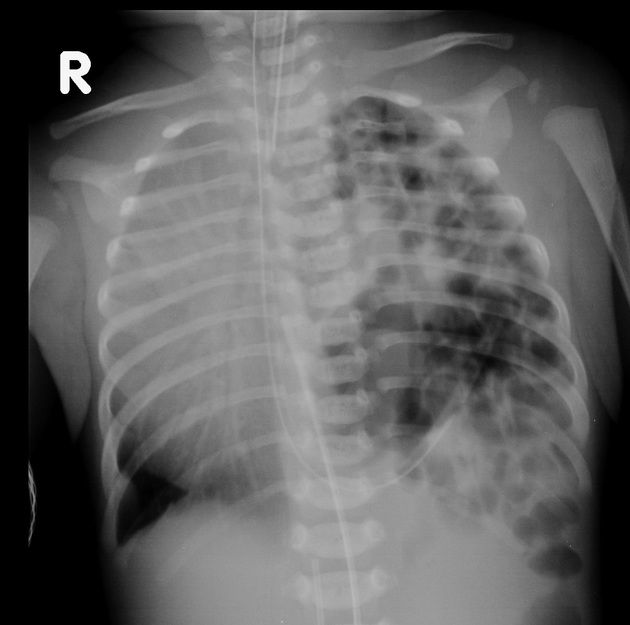

Hình 2. Hình ảnh Xquang ngực của trẻ bị thoát vị hoành bẩm sinh

• X quang phổi có bóng hơi dạ dày hay ruột trong lồng ngực, trung thất bị đẩy về bên đối diện, không thấy vòm hoành.